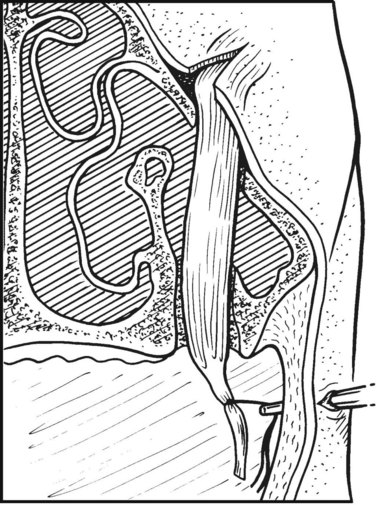

Foals should be evaluated carefully for aspiration pneumonia and to rule out associated congenital defects. The degree of the deformity can be determined by oral radiographic examination, and computed tomography of the skull might be useful to confirm the position and degree of premaxillary/maxillary deviation and nasal obstruction (Fig. 19.15). Dental impressions of the upper and lower arcades from the premolars to the incisors can help the surgeon determine the amount of space created on the concave side of the premaxillae/maxillae when the deformity is corrected and the upper and lower incisor arcades are brought into proper occlusion (Fig. 19.16). Occlusal abnormalities of the premolars causing wear should be corrected prior to surgery. This involves re-establishing a normal occlusal angle on the premolar arcades and leveling the incisors (Fig. 19.17).

image

Fig. 19.15 Computed tomography images of transverse scans through the head of a 7-month-old Thoroughbred filly with wry nose. The filly is positioned in dorsal recumbency, and serial images, beginning at the second premolar and advancing rostrally, demonstrate the premaxillary curvature and progressive narrowing of the right nasal cavity.